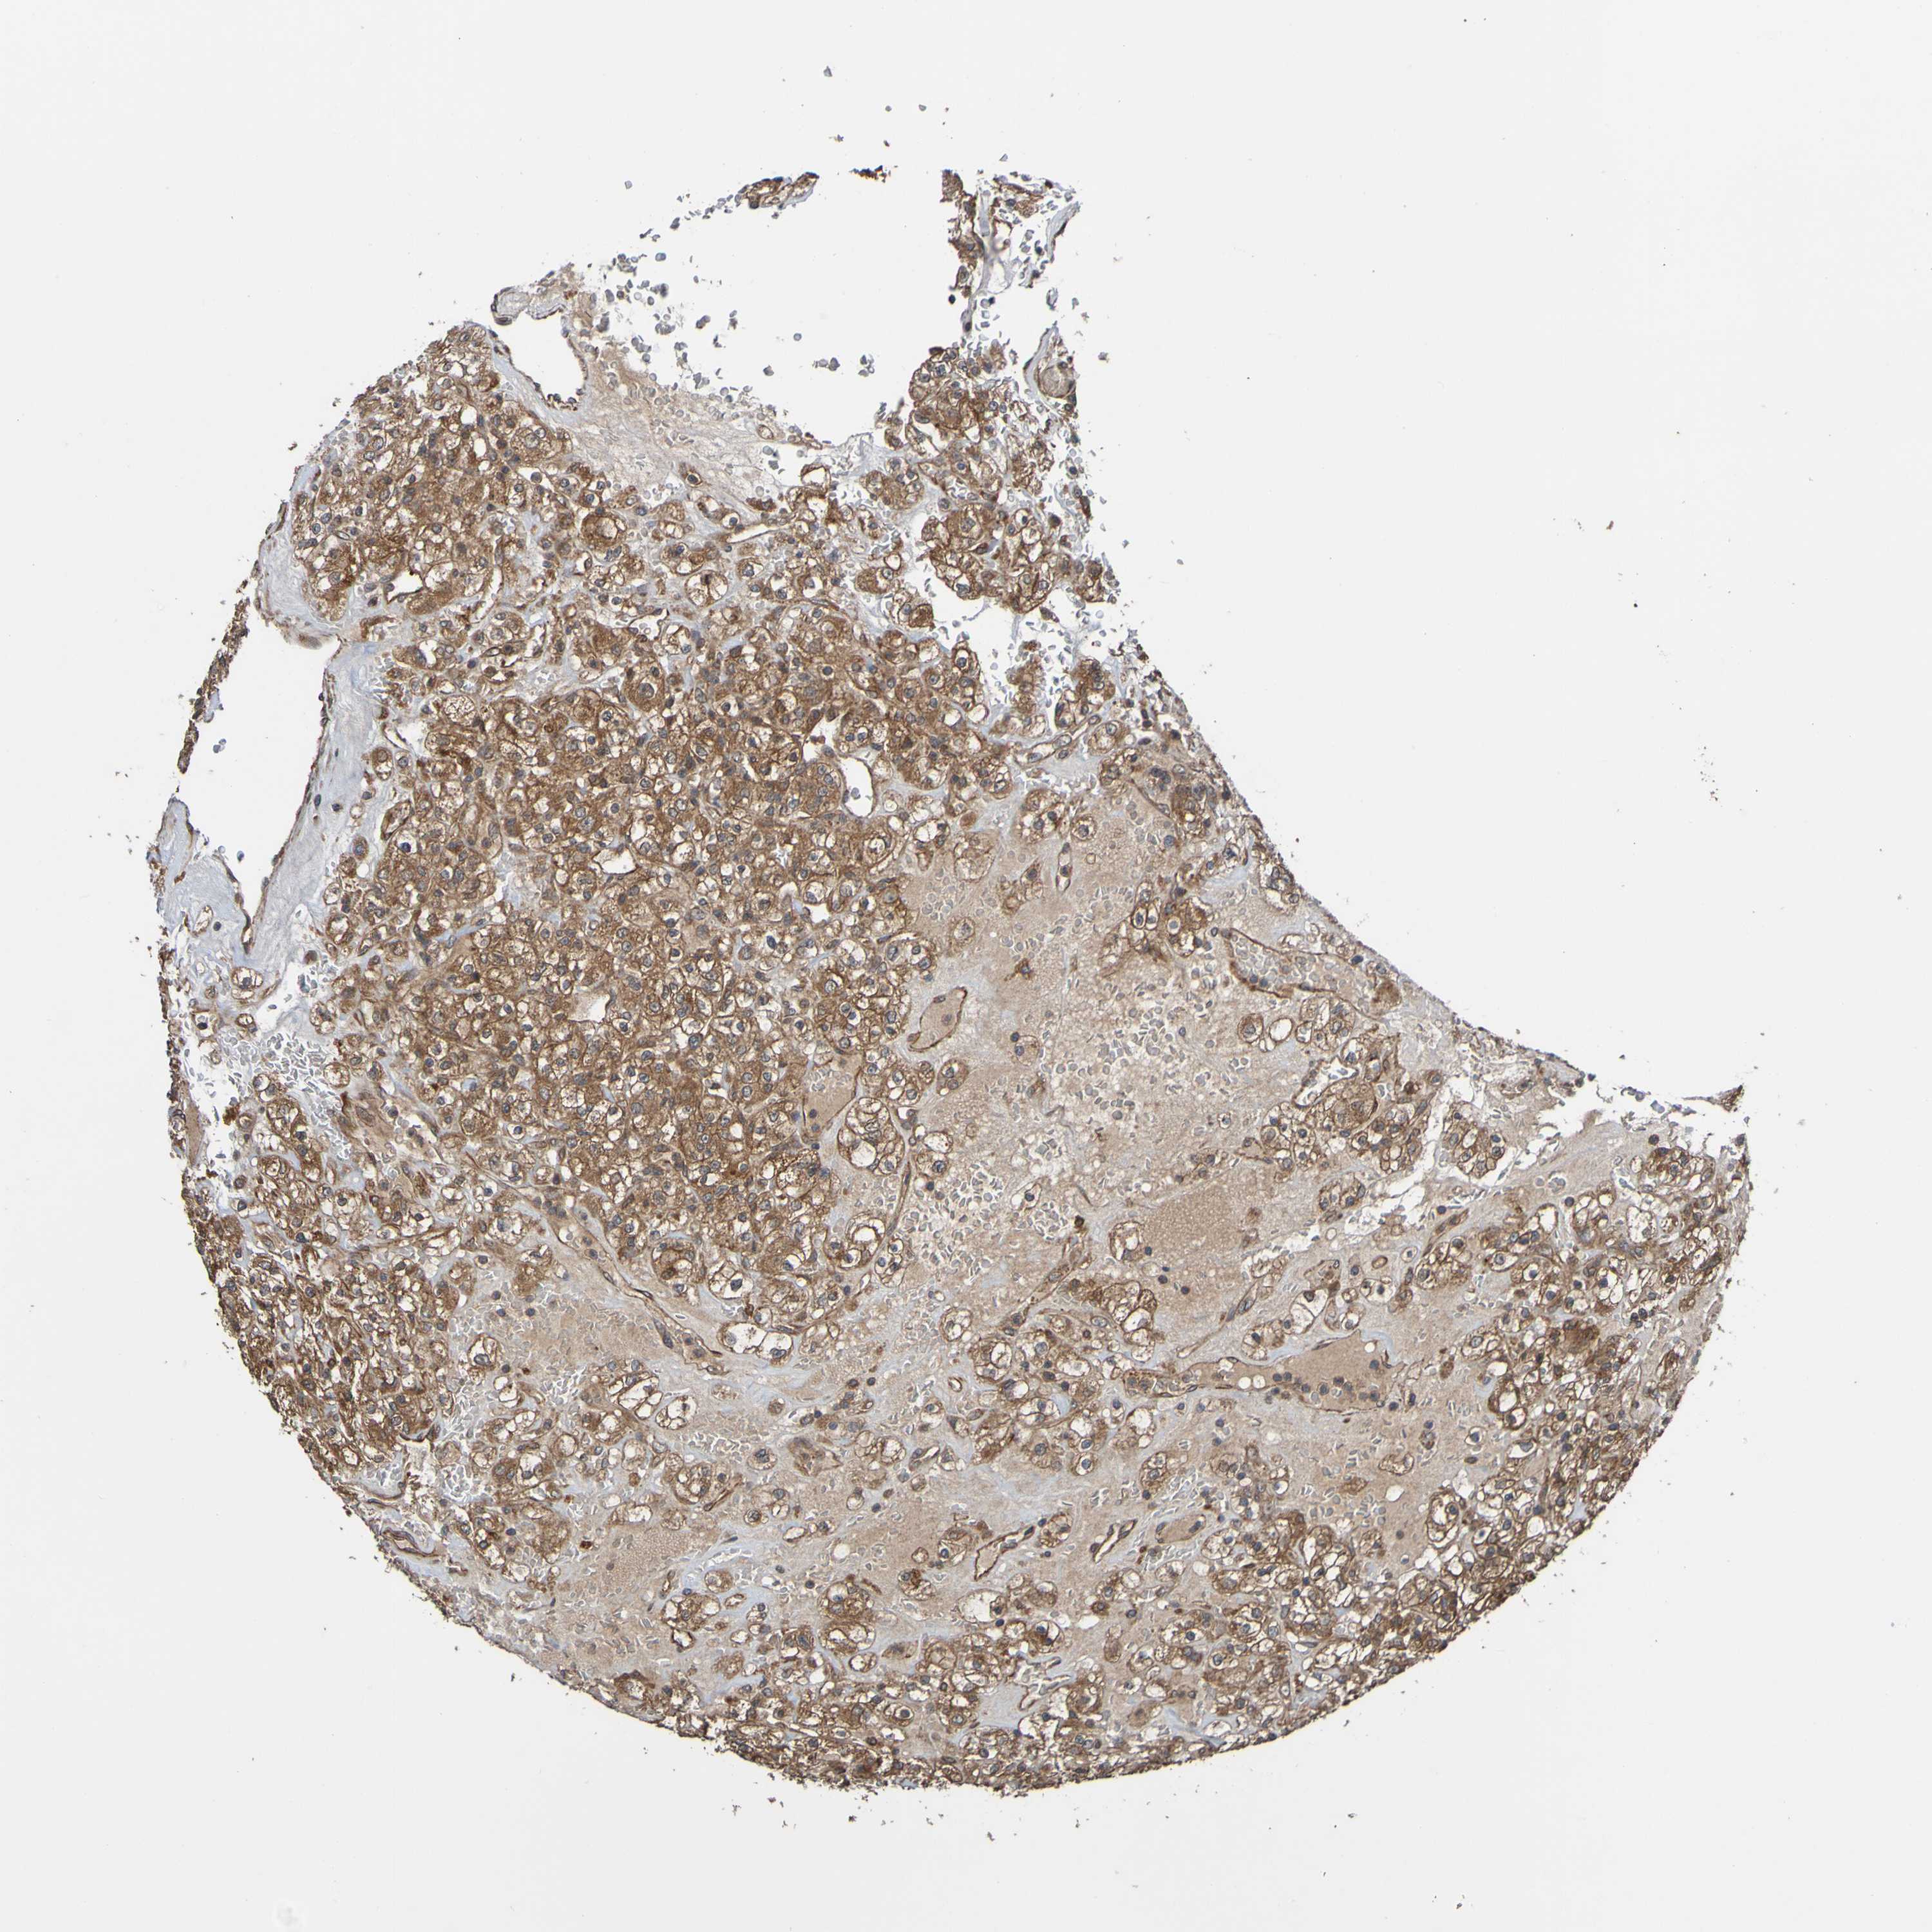

KIDNEY RENAL CLEAR CELL CARCINOMA (VALIDATION) - Interactive survival scatter ploti

The Survival Scatter plot shows the clinical status (i.e. dead or alive) for all individuals in the patient cohort, based on the same data that underlies the corresponding Kaplan-Meier plots. Patients that are alive at last time for follow-up are shown in blue and patients who have died during the study are shown in red.

The x-axis shows the expression levels (FPKM) of the investigated gene in the tumor tissue at the time of diagnosis. The y-axis shows the follow-up time after diagnosis (years). Both axes are complimented with kernel density curves demonstrating the data density over the axes. The top density plot shows the expression levels (FPKM) distribution among dead (red) and alive patients (blue). The right density plot shows the data density of the survived years of dead patients with high and low expression levels respectively, stratified using the cutoff indicated by the vertical dashed line through the Survival Scatter plot. This cutoff is automatically defined based on the FPKM cutoff that minimizes the p-score. The cutoff can be changed by dragging the vertical line or by entering a cutoff value in the square labeled "Current cut-off".

Under the Survival Scatter plot the p-score landscape (black curve; left axis) is shown together with dead median separation (red curve; right axis). Dead median separation is the difference in median mRNA expression between patients who have died with high and low expression, respectively. It is calculated as follows: median FPKM expression of dead patients with high expression - median FPKM expression of dead patients with low expression. This is intended to aid the user in visually exploring custom cutoffs and the associated p-scores and dead median separation.

Individual patient data is displayed and can be filtered by clicking on one or more of the category buttons on the top of the page. Categories describing expression level and patient information include: high, low, alive, dead, female, male and tumor stages. The scale of the x-axis can be toggled between linear and log-scale by clicking on the "x log" button. Mouse-over function shows TCGA ID, patient information and mRNA expression (FPKM) for each patient.

& Survival analysisi

Kaplan-Meier plots summarize results from analysis of correlation between mRNA expression level and patient survival. Patients were divided based on level of expression into one of the two groups "low" (under cut off) or "high" (over cut off). X-axis shows time for survival (years) and y-axis shows the probability of survival, where 1.0 corresponds to 100 percent.

UCN is not prognostic in Kidney Renal Clear Cell Carcinoma (validation)

: 2.5

: N/A

N/A

TCGA RNA samplesi

RNA-seq data is reported as average FPKM (number Fragments Per Kilobase of exon per Million reads), generated by the The Cancer Genome Atlas (TCGA) .

Normal distribution across the dataset is visualized with box plots, shown as median and 25th and 75th percentiles. Points are displayed as outliers if they are above or below 1.5 times the interquartile range. FPKM values of the individual samples are presented next to the box plot.

Average pTPM 3.7

Number of samples 100